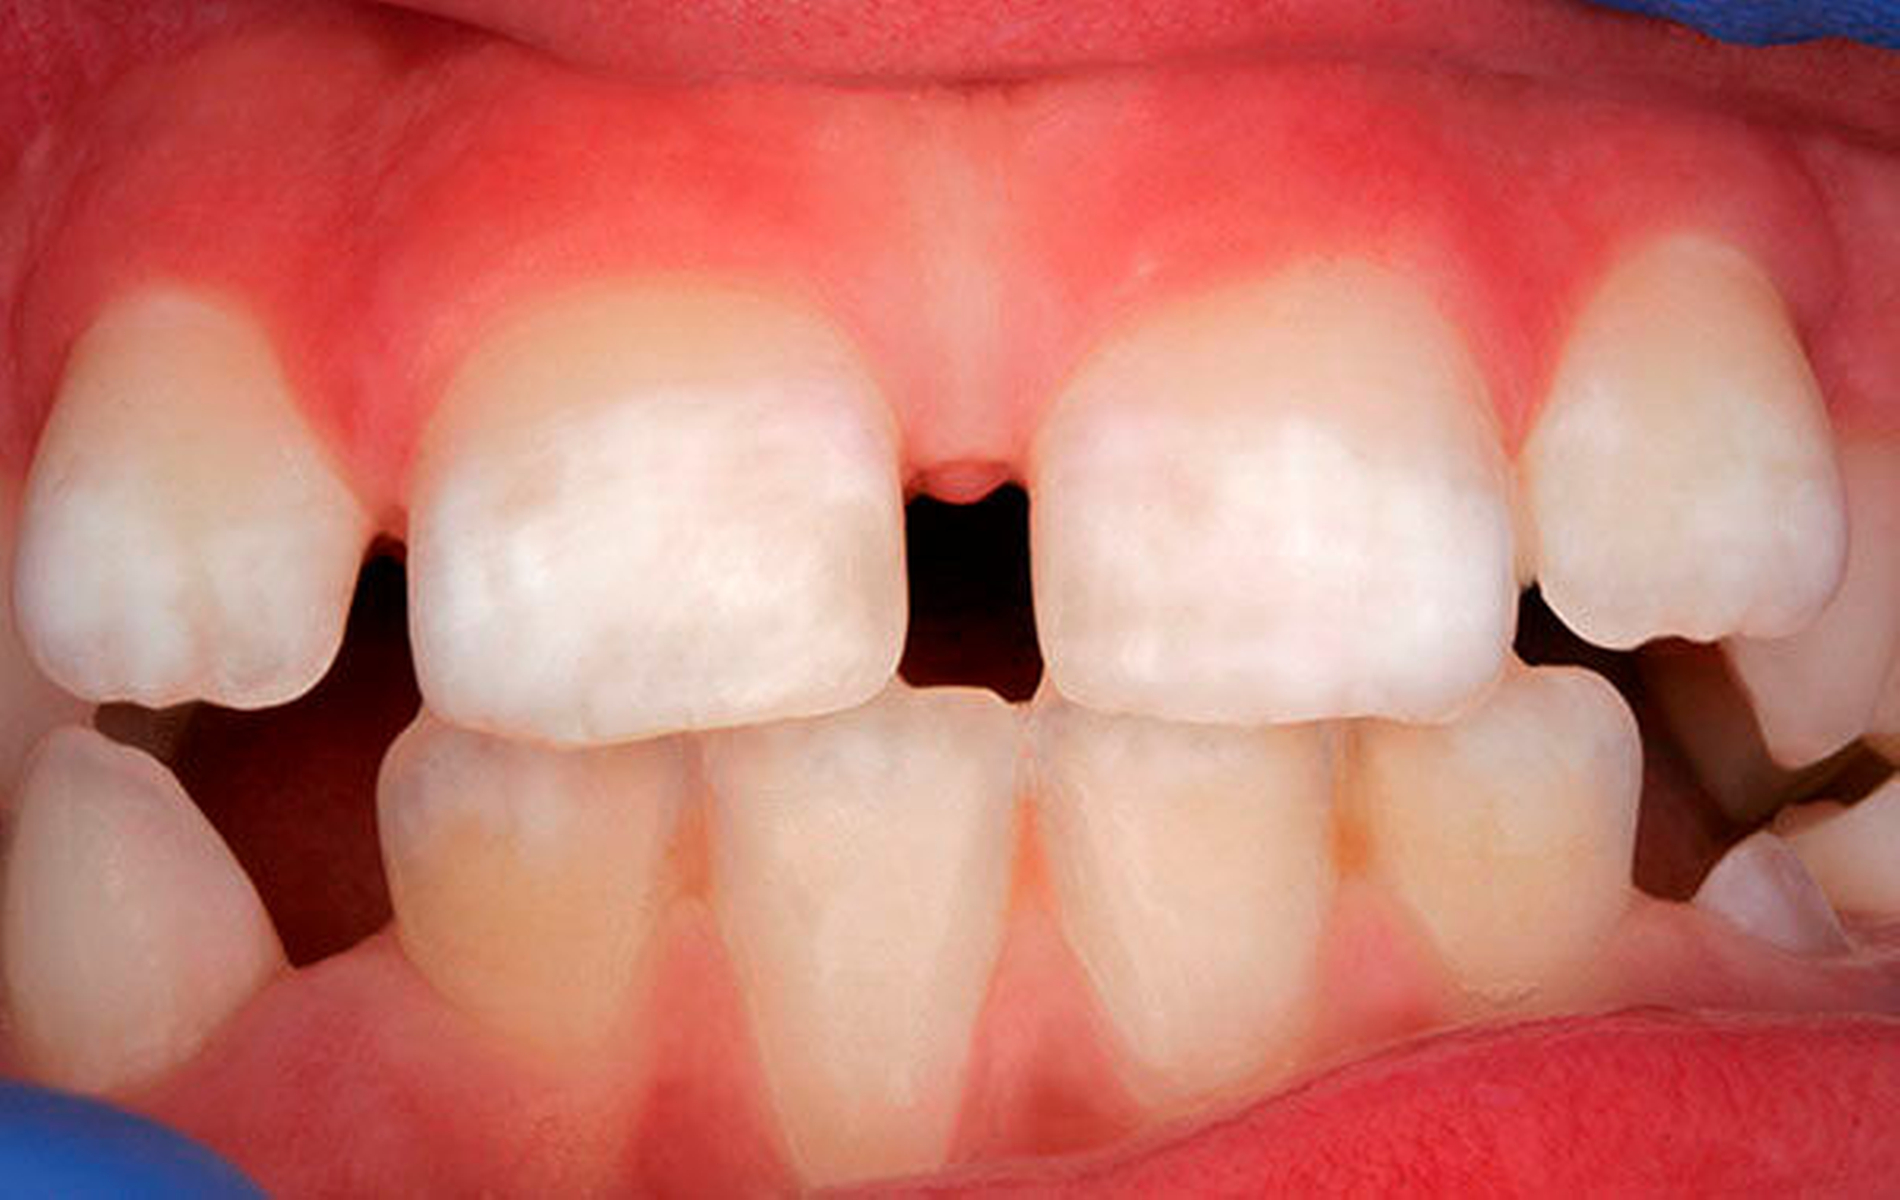

Die Gefahr von klinisch relevanten Dentalfluorosen (Abbildung 3) besteht bis zum Alter von sechs bis sieben Jahren, da bis dahin alle bleibenden Zähne im sichtbaren Bereich mineralisiert sind. Somit ist bis zu diesem Alter die Fluoridnutzung sorgfältig zu kontrollieren. Bei 0,05 bis 0,07 mg Fluorid pro kg Körpergewicht kommt es bei einem Teil der Kinder zu sehr leichten, weißlichen Schmelzflecken [Angmar Manson und Whitford, 1982; Baelum et al., 1987]. Das Risiko für die permanenten Frontzähne ist bei Kleinkindern am höchsten, da sie ein geringes Körpergewicht aufweisen und damit die kritische Dosis niedrig liegt. Außerdem verschlucken sie einen Teil der Kinderzahnpaste.

Insgesamt stehen zur Kariesprävention zahlreiche Fluoridpräparate zur Verfügung, aber bei Kleinkindern sollte die Aufnahme von erhöhten Dosen ausgeschlossen werden. Aufgrund der Gefahr des unkontrollierten Verschluckens ist der Einsatz von Mundspüllösungen oder Fluoridgelen daher bei Kleinkindern nicht sinnvoll. Der regelmäßige ordnungsgemäße Gebrauch von Kinderzahnpasten führt bei einer Kontrolle der anderen Fluoridquellen, insbesondere bei Ausschluss der systemischen Zufuhr über Tabletten, nicht zur Dentalfluorose (Abbildung 3).